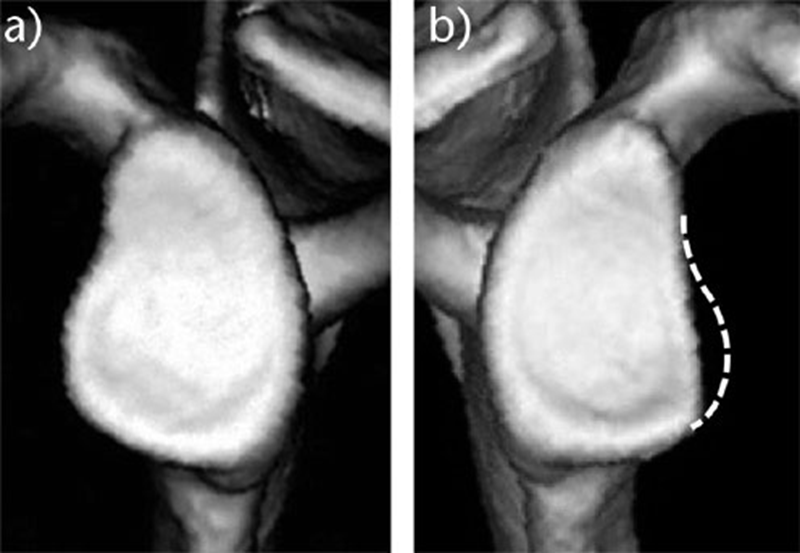

②对侧法:对侧肩(A),如果完好无损,可作为对照(虚线)(B)。